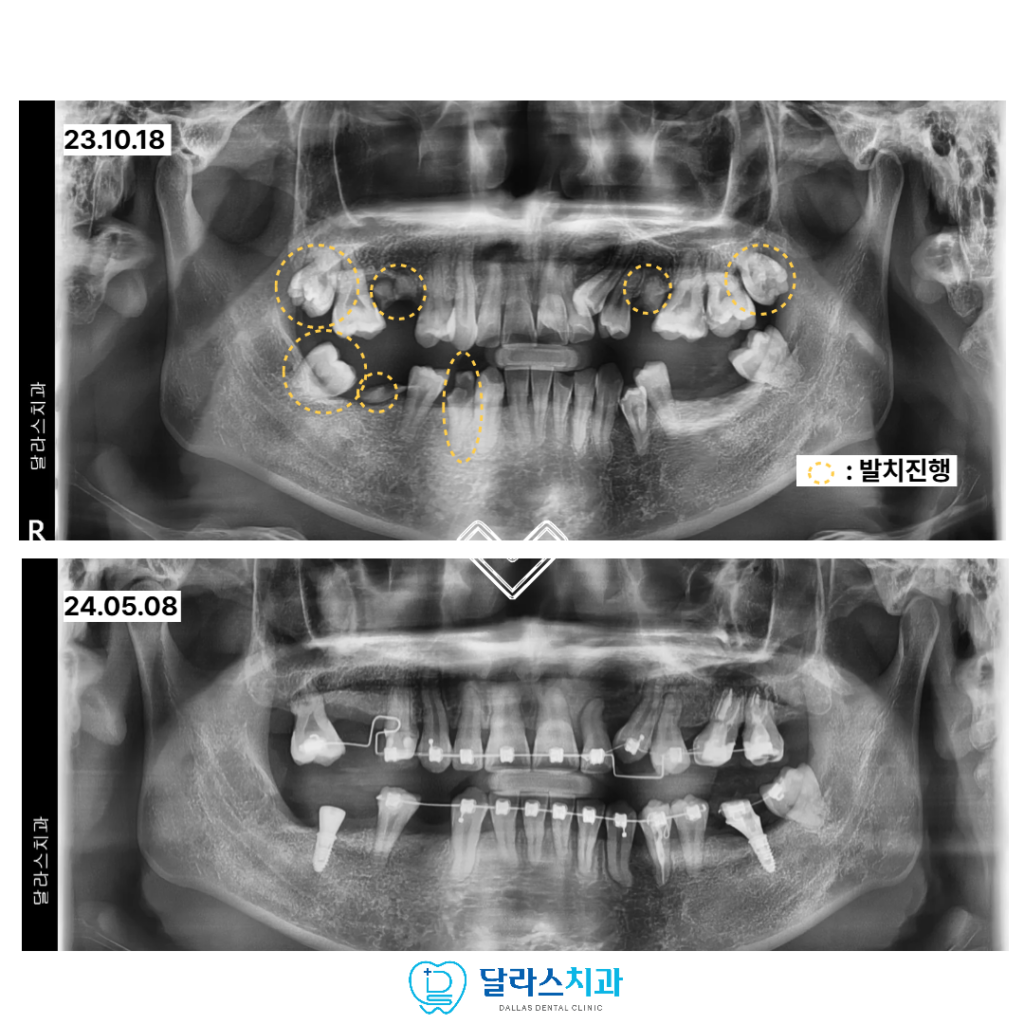

충분한 상담과 진단 끝에 꼭 필요한 범위 내에서 발치를 결정하고

교정 치료를 시작하였으며 동시에 임플란트 치료를 병행하는 계획을 세웠습니다.

교정 치료와 임플란트 치료를 동시에 진행할 수 있다는 점은

치료 기간과 부담을 줄이는 데 큰 도움이 되었고

환자분 역시 비교적 편안한 마음으로 치료에 임할 수 있었습니다.

노원치과 치료 과정에서는 어금니의 지지 역할을 회복하는 데 중점을 두어

교합을 안정적으로 만들어 주었고,

턱이 가장 편안한 위치에서 물릴 수 있도록

기준이 되는 교합 위치를 설정한 뒤 치료를 진행하였습니다.

또한 발치 치아를 가능한 줄이기 위해

아래쪽 사랑니를 교정적으로 이동시켜 새로운 교합 관계를 형성하였고

이를 통해 기능적인 균형을 보다 안정적으로 완성할 수 있었습니다.

총 치료기간은 약 2년으로,